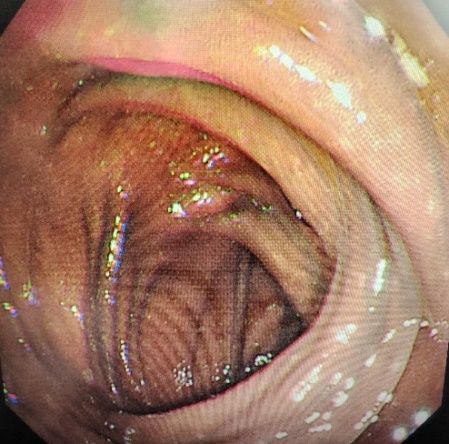

血液内科团队立即对黄玲进行了驱砷治疗,并且需要长期监测肿瘤的发生风险。医生们考虑到长期服用雄黄还可能造成结肠黑变病,还为她进行了肠镜检查。果不其然,肠镜检查显示,黄玲的整个大肠呈黑褐色,也就是结肠黑变病。